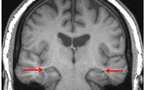

El cerebro de los invidentes es diferente al de las personas que ven - 20/11/2009

Científicos de la Universidad de California en Los Ángeles han realizado un estudio, con una tecnología de registro de imágenes cerebrales altamente sensible, cuyos resultados han confirmado que el cerebro de los invidentes es distinto al de las personas que ven. El cerebro de los ciegos se transforma anatómicamente y cambia su volumen en ciertas regiones, para que éstos compensen la pérdida de visión con nuevas capacidades.